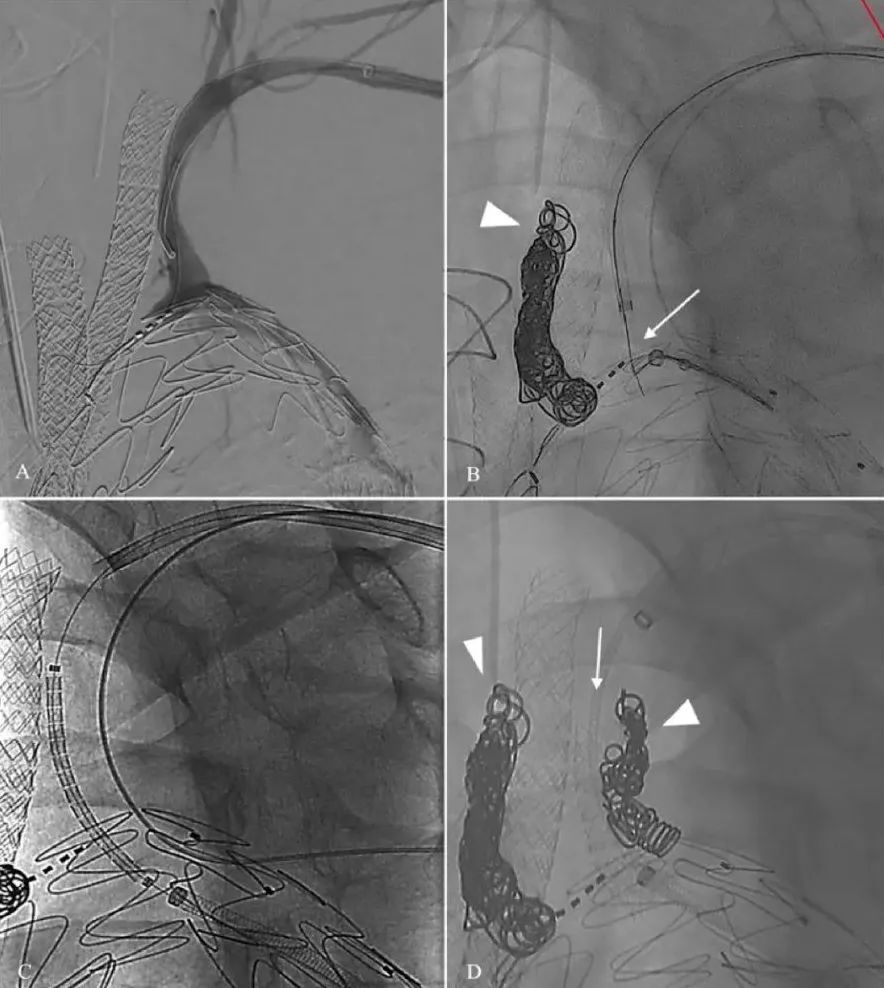

图1

血管造影显示带电导丝对内膜片开孔(A)。DSA显示在真腔放置了一个分支支架。白色箭头显示导管处于分离真腔和假腔的内膜片上(B)(C)。透视图显示,以猪尾巴导管为目标,带电导丝(白色三角)穿过内膜片(D)。导丝被捕获(E)。右肾动脉桥接球扩覆膜支架(F)。DSA显示桥接支架成功穿过内膜片进入RRA。